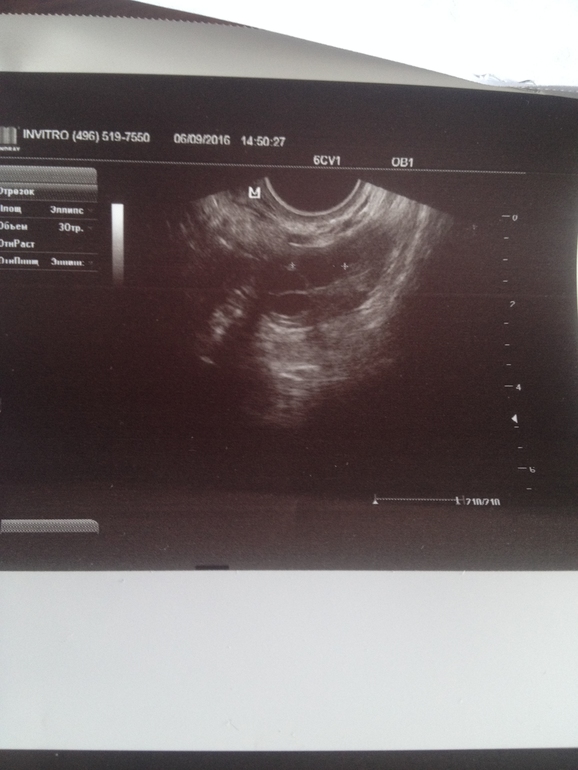

Сегодня на 28 ДЦ пошла на УЗИ (в другое место), т.к. 2 дня очень обильные выделения ЯБ. В результате эндометрий 13мм, в ЛЯ формируется желтое тело 20х22мм, небольшое кол-во жидкости есть. Узистка сказала, что прямо сейчас происходит овуляция, ЖТ только начало формироваться.

Это как понимать? За 4 дня фоллик с 11мм так вырос и совулировал? посмотрите фотки, плиз, кто понимает, я в этом полный профан. И как думаете в постель уже поздно ложиться?

А подскажите кто разбирается ЖТ на каком из этих фото?

на снимках не видно жт

на первом фото у вас 100% фолликулы.

на 3 фото матка.